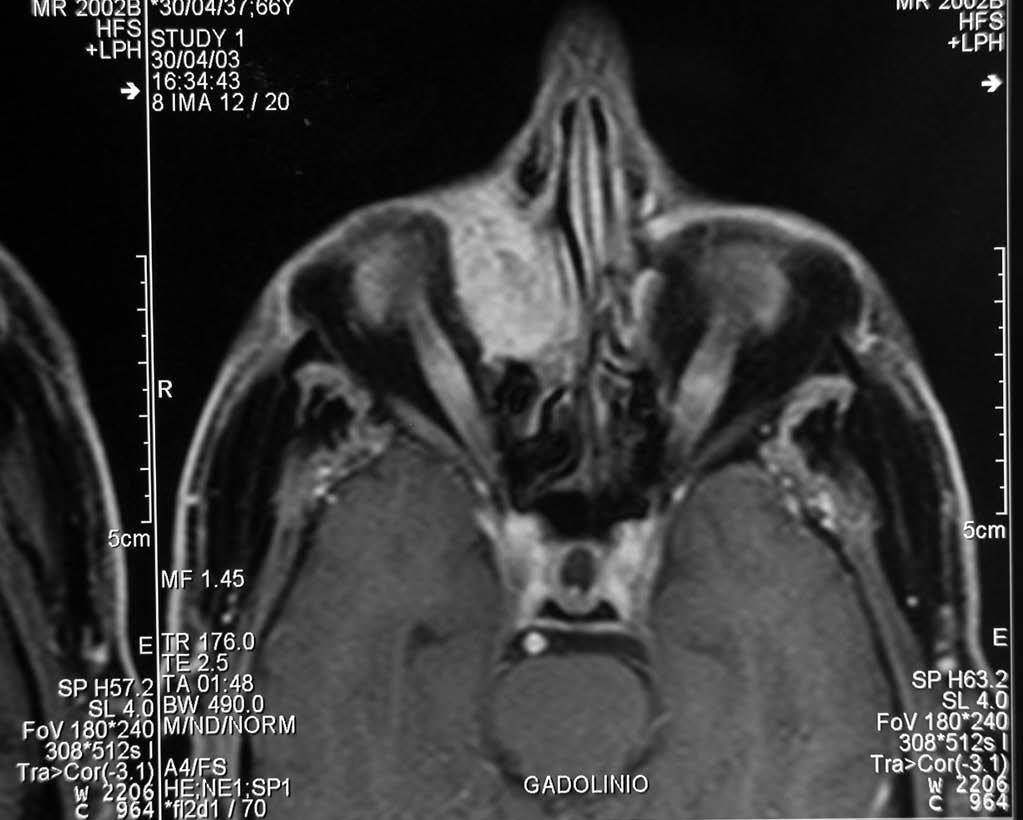

Se llevó a cabo una exéresis parcial de la lesión con fines diagnósticos y posteriormente se realizó una RM, que mostró (figs. 3 y 4) una mínima infiltración de la grasa orbitaria adyacente a la tumoración y descartó la afectación de la musculatura extrínseca ocular.

Fig. 3.--Resonancia magnética realizada tras la resección parcial del tumor. Se muestra un plano axial, secuencia potenciada en T1 con saturación grasa y tras administración de contraste paramagnético. La tumoración de la órbita derecha muestra un realce intenso y homogéneo.